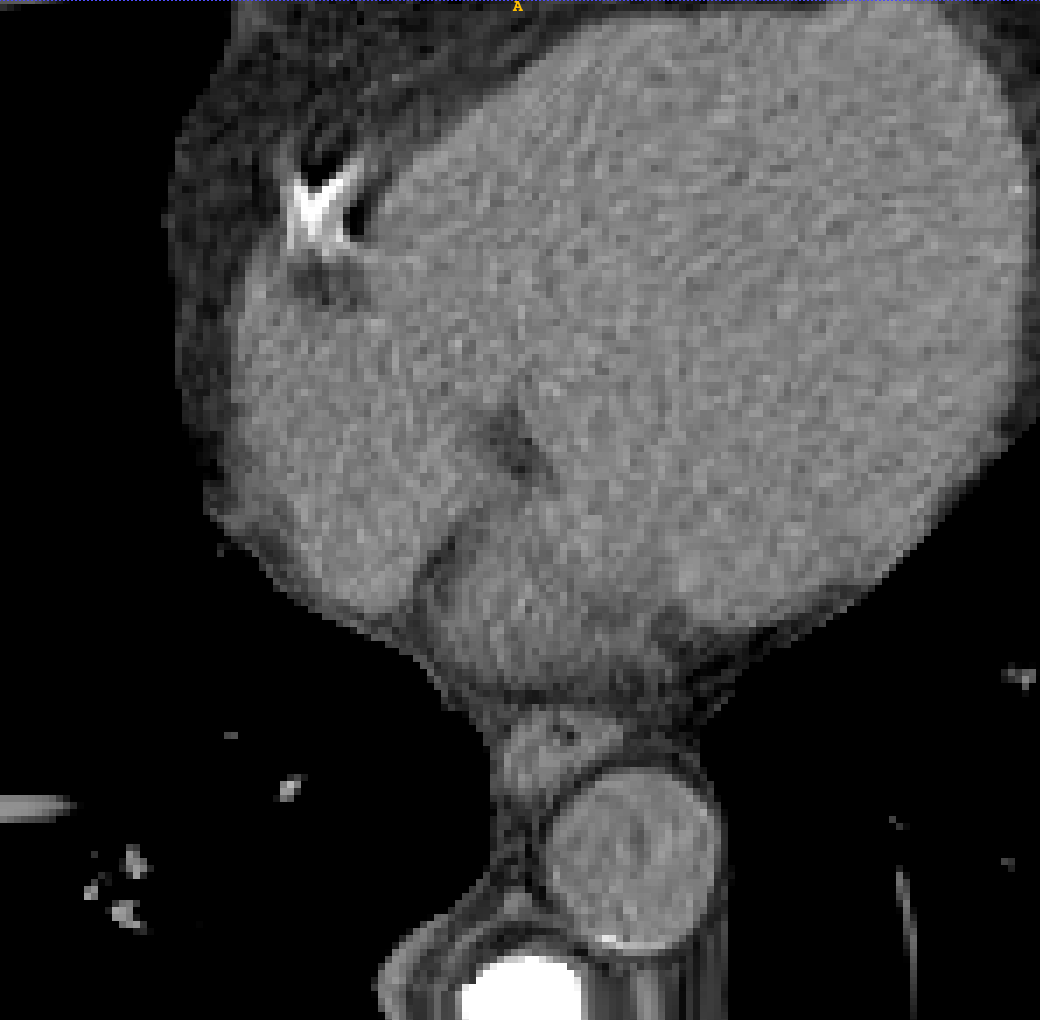

TABLE V: Visualization result on SegTHOR. Gray image registration result(row 1-2) shows the fitting ability of various methods. Mask image registration result(row 3-4) shows the regional continuity of various methods. The mask includes four parts: heart(green), aorta(yellow), trachea(blue) and esophagus(red).

[Uncaptioned image] [Uncaptioned image] [Uncaptioned image] [Uncaptioned image] [Uncaptioned image] [Uncaptioned image]

F M VoxelMorph Ants deedsBCV Ours

We selected four images of large deformations occurring at different locations from different CT, the visualization results are shown in Table V.

Rows 1-2 shows the CT gray image registration results. The task is to register MM to FF. From the visualization of gray image results, we can see that although ANTs and deedsBCV has high dice scores, the visualization results look unrealistic. Meanwhile, deep learning methods look smoother. The sixth column shows the results of our method. The fitting effect is improved compared to previous methods.

Rows 3-4 shows the mask registration results. The background of each image is FF. We could judge the performance by observing the fitting degree of the mask and background. In many practical tasks, we use a registration algorithm to register MM’mask to get the mask of FF. There may be a situation where the gray image fitting is good, but the mask result is poor. This may be because the continuity of the registration field is not good enough.